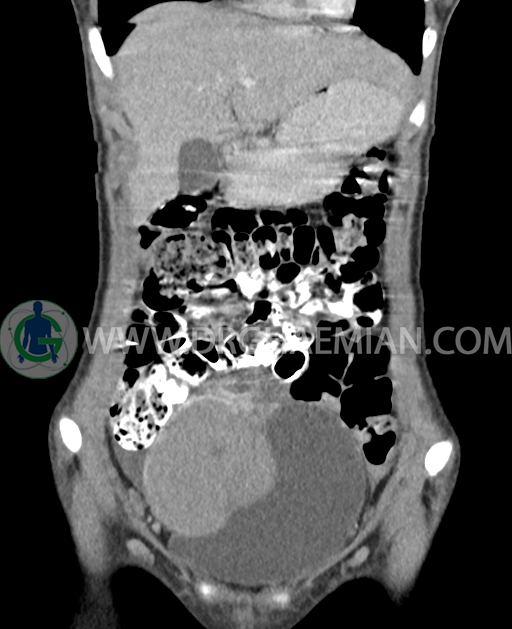

سی تی اسکن شکم و لگن از تشعشعات برای ایجاد تصاویر عرضی مقطعی از نایحه شکم و بین استخوان های لگن استفاده می کند. در این کیس تومور سلول زایا به ابعاد mm 125 x 112 x 80 دیده می شود.

در سی تی اسکن اسپیرال شکم و لگن با کنتراست خوراکی و وریدی (مولتی دیدکتور 16 با مقاطع ظریف و بازسازی های ساژیتال و کرونال) :

توده هیپردنس لوبوله بزرگ به ابعاد 125x112x80mm حاوی نواحی سیستیک داخلی و enhancement قابل توجه پریفرال همراه با آسیت متوسط در فضای شکم و لگن با احتمال بیشتر با منشا از تخمدان راست، درون لگن دیده می شود که در درجه اول مطرح کننده germ cell tumor می باشد .